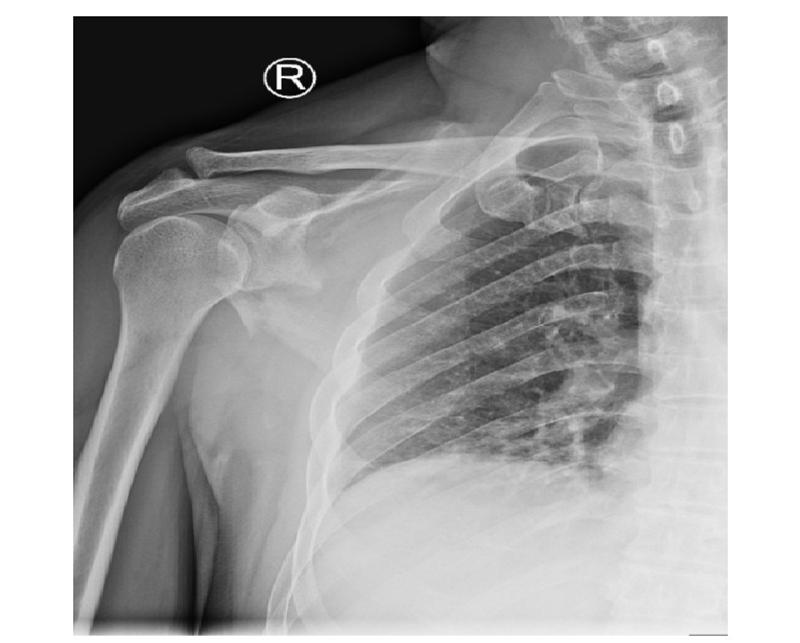

病例4为53岁男性患者,因高处坠落导致右肩胛骨骨折,合并右侧第3、5、7、8肋骨骨折(图20-21)。

图20 术前X线片示肩胛颈及肩胛骨体部骨折

图21 术前CT三维重建示肩胛颈及肩胛骨体部骨折 图A:肩胛骨前面观;图B:肩胛骨侧面观

术中采用钢板固定肩胛颈内下方骨折块,肩胛骨体部骨折固定采用缝线辅助固定技术,骨折端以Nice结固定。术后CT三维重建显示骨折复位满意,固定良好(图22)。